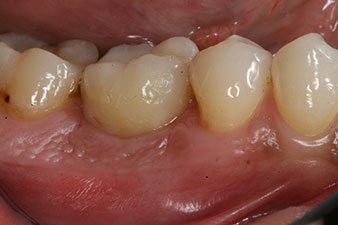

Fig. 6 : Dix semaines plus tard, on a retiré le façonneur de gencive qui avait été inséré après la pose de l’implant. Dans la direction linguo-buccale, la valeur ISQ est restée pratiquement inchangée, à 63 (sonde de mesure à proximité, à une distance de 2-3 mm).

L’implant a été mis à nu deux mois plus tard et un façonneur gingival a été introduit par vissage (pas de photo).

Après cicatrisation des tissus mous, la stabilité de l’implant a été mesurée une nouvelle fois avant la pose de la restauration prothétique.

Les deux valeurs étaient pratiquement inchangées, situées entre la plage moyenne et la plage haute - la valeur la plus basse étant toujours utilisée comme valeur de référence qui détermine le traitement.

Par conséquent, il a été possible d’enregistrer une ostéo-intégration réussie et une stabilité biologique correcte, permettant également de prendre une empreinte durant la même séance.